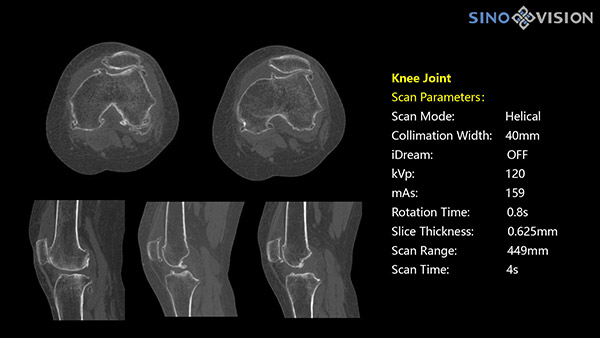

Инновационный 128-срезовый компьютерный томограф SinoVision InsitumCT 568 – это сочетание высокой скорости работы, низкой дозы и максимума возможностей для подавляющего большинства клинических случаев, как в рутинных, так и в углубленных специализированных исследованиях, в том числе педиатрические и кардиологические исследования при сверхнизких дозах.

Полнофункциональный 128-резовый компьютерный томограф InsitumCT 568 - это лучшее в новом поколении широкодиапазонных томографов с 128 срезами и большой диафрагмой. Этот КТ-сканер с большой апертурой обеспечивает 128 срезов КТ с диафрагмой 76 см, улучшает разрешение изображения до 21Lp/cm, помогает точно диагностировать и лечить заболевания, а также значительно улучшает клинические характеристики и расширяемость оборудования. Позволяет реализовать визуализацию в высоком разрешении и в малых дозах лучевой нагрузки.

- Толщина среза: 0.625 мм

Характеристики сканирования

- Минимальное время одного оборота рентгеновской трубки: От 0.48 до 2 сек